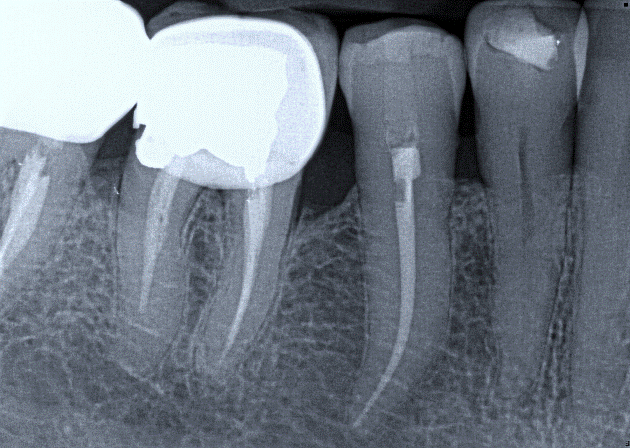

Tooth 4.8 is planned for extraction. Which radiographic findings suggest an increase in the degree of difficulty of the extraction?

13. (Select ONE OR MORE correct answers.)

Tooth 1.8 is planned for surgical extraction. Which radiographic findings suggest an increase in the degree of difficulty of the extraction?

Tooth 2.8 is planned for surgical extraction. Which radiographic findings suggest an increase in the degree of difficulty of the extraction?